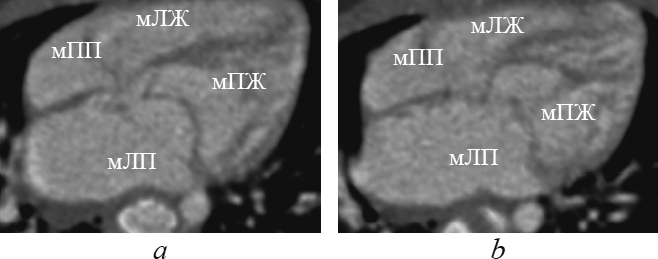

Анатомические признаки ушка, характерного для морфологически левого предсердия (узкая вытянутая форма с заостренным концом, узкое соединение с предсердной полостью, хорошо выраженная дольчатость [1, 2, 4, 16]), определяют в реформации левых камер сердца (рис. 2). В этой реформации обращает на себя внимание соединение морфологически левого предсердия с морфологически левым желудочком при транспозиции (рис. 2, а), соединение морфологически левого предсердия с морфологически правым желудочком при корригированной транспозиции (рис. 2, b).

Рис. 2. В реформации левых камер сердца ушко морфологически левого предсердия при транспозиции магистральных сосудов (а, стрелка), при корригированной транспозиции магистральных сосудов (b, стрелка)

Fig. 2. Left heart chambers reformation. The eyelet of the morphologically left ventricle in great arteries transposition (a, arrow) and in corrected great arteries transposition (b, arrow)